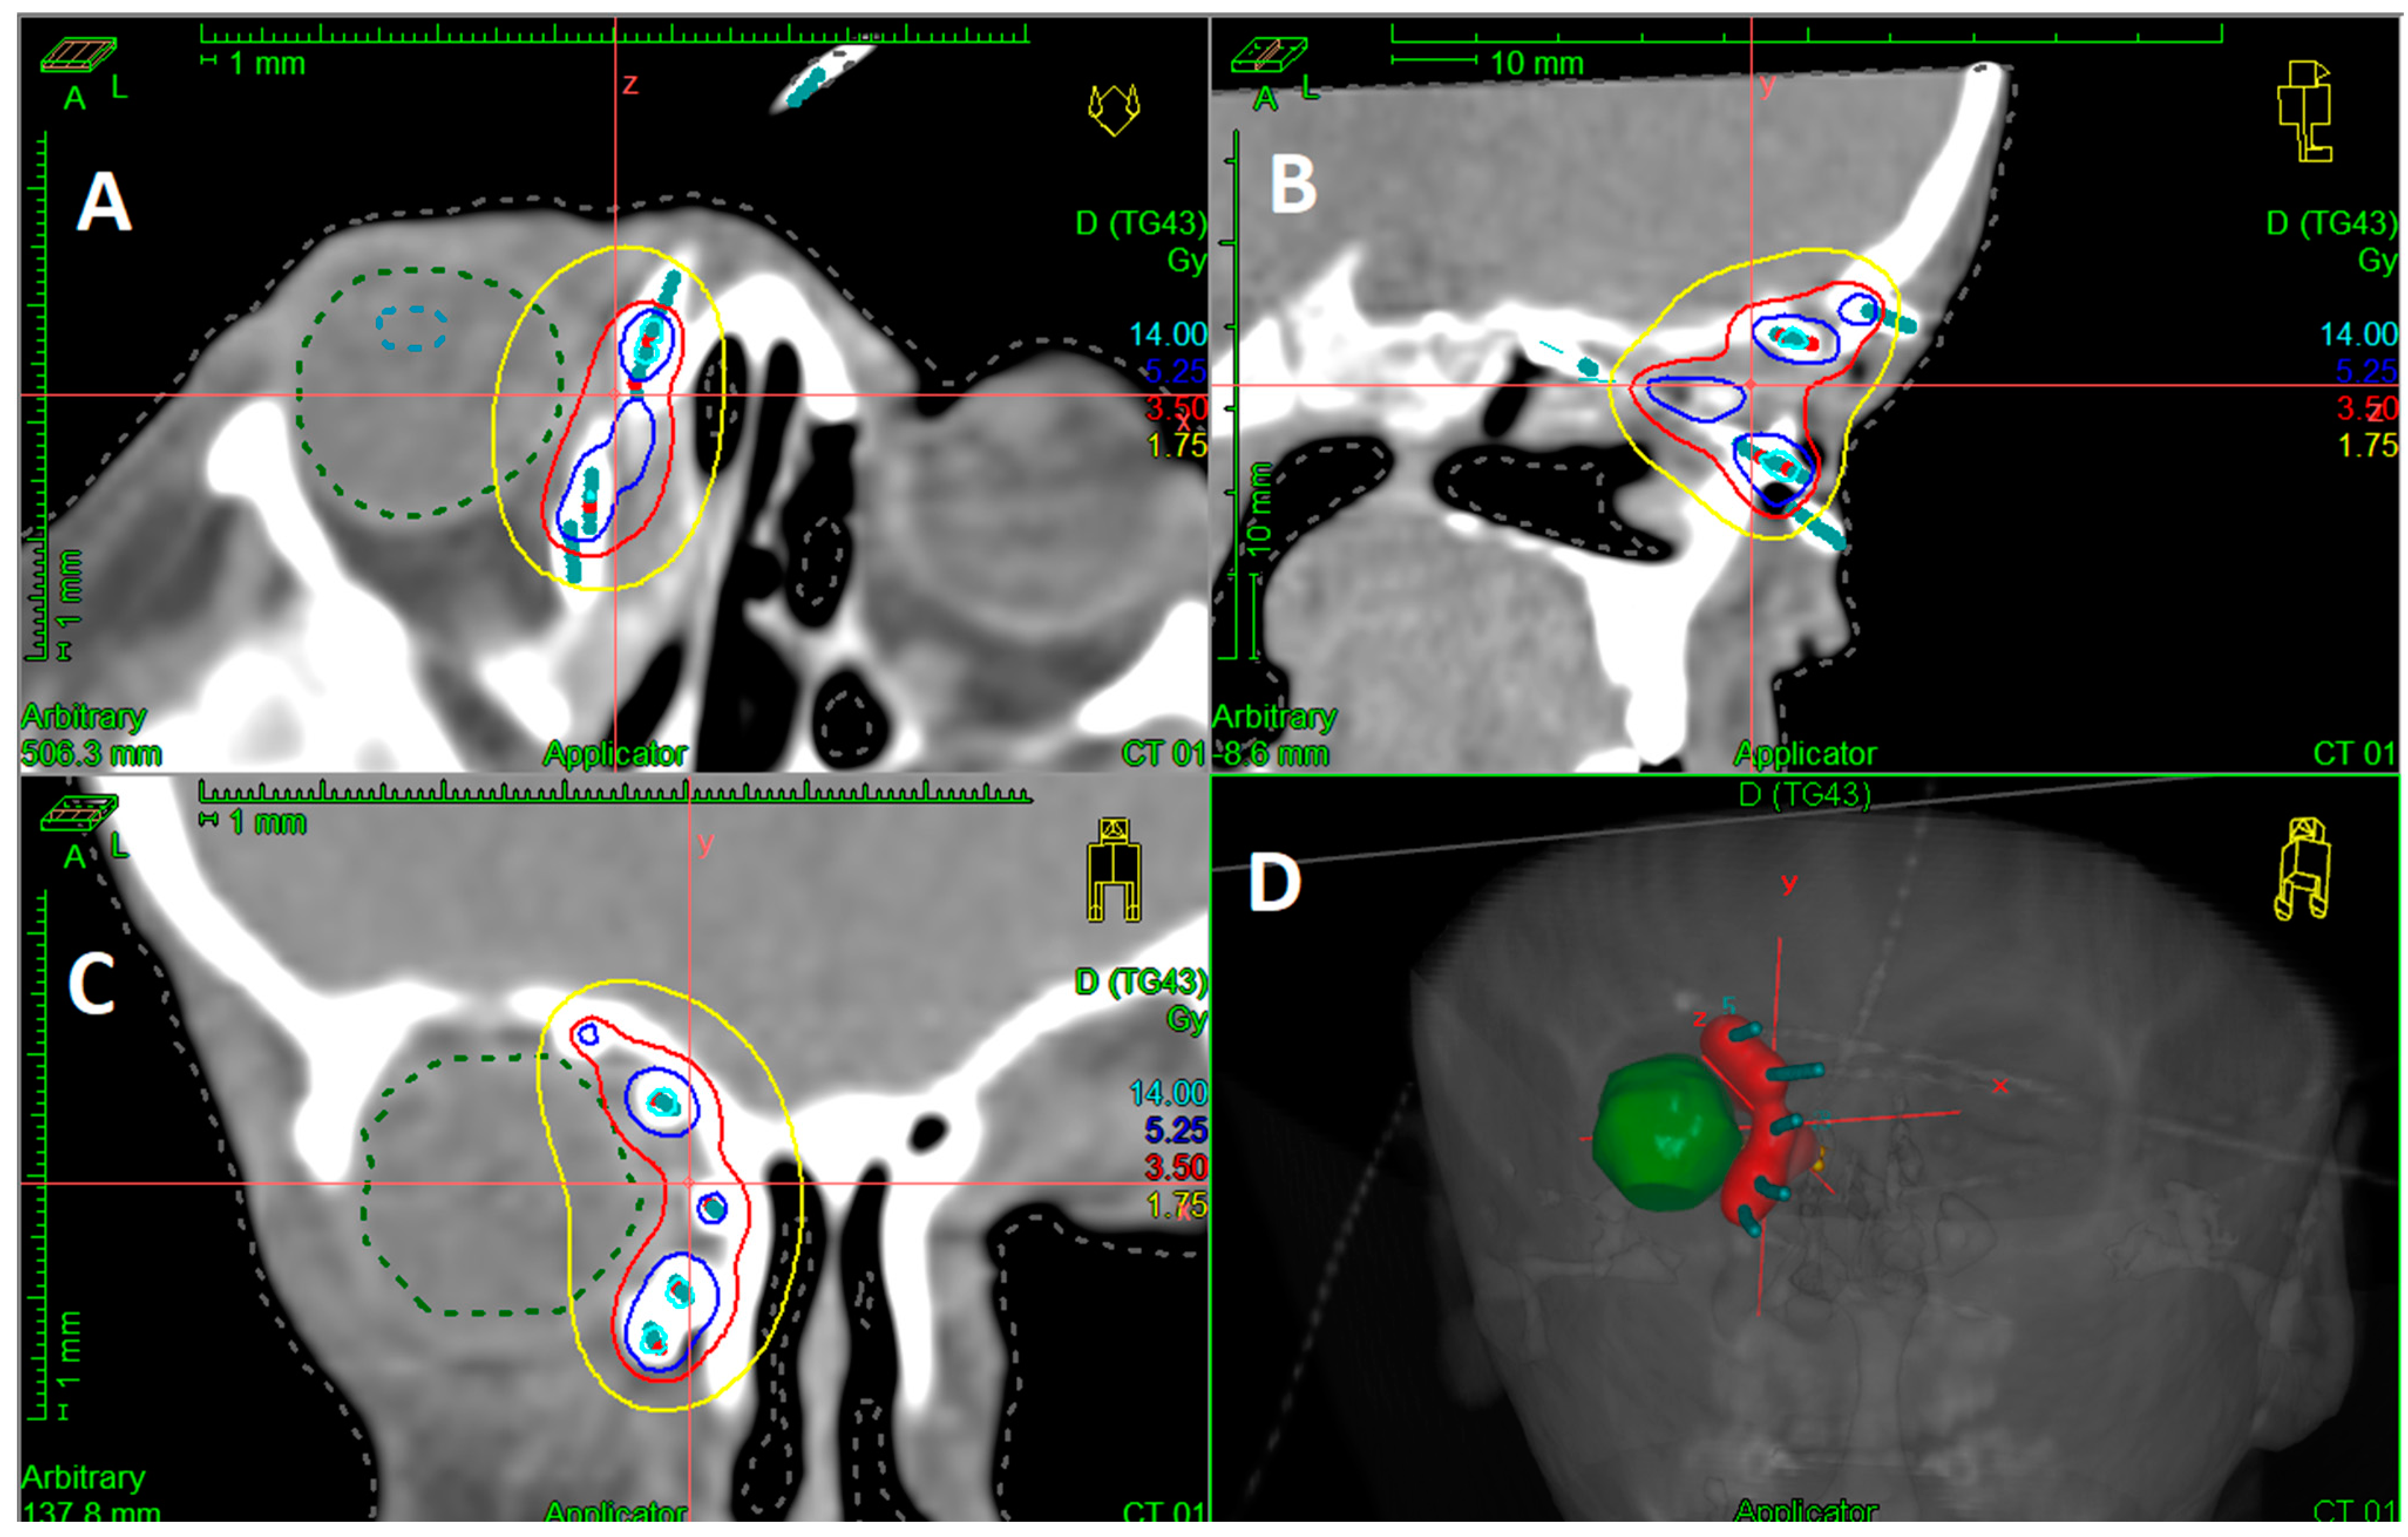

2.2. Interventional Radiotherapy (Brachytherapy)

3.4. HDR-IRT Treatment Characteristics